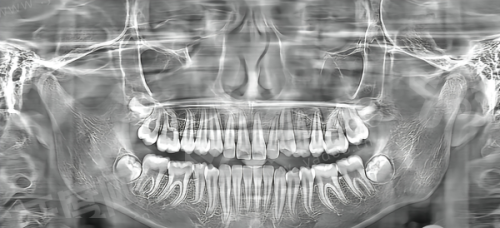

该说法多针对传统固定局部义齿(固定桥)修复单颗牙缺失的常规操作:当单颗牙齿缺失时,需将缺牙间隙两侧的健康天然牙作为基牙,制作三颗连为一体的修复体覆盖缺失牙位置与两侧基牙,因此被俗称为“镶一颗包两颗”。

目前已有多种无需磨损邻牙的镶牙方案,比如活动义齿依靠基托、卡环吸附或卡抱邻牙/黏膜固位,不需要磨除健康邻牙;种植牙则是将钛合金植体植入牙槽骨,待骨结合后安装基台与牙冠,模拟天然牙牙根结构,同样不会损伤邻牙。

1、传统镶牙包括固定桥与活动义齿:固定桥依靠磨除邻牙作为基牙固位;活动义齿依靠基托、卡环吸附或卡抱邻牙/黏膜固位。

2、种植牙:将钛合金植体植入牙槽骨,待骨结合后安装基台与牙冠,模拟天然牙牙根结构。